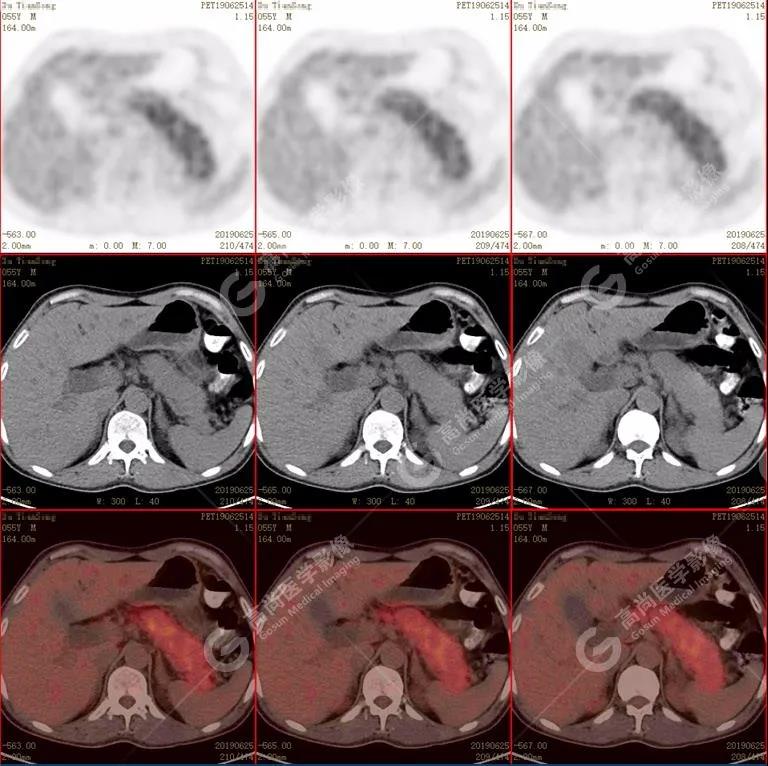

胰腺腫脹、密度均勻,代謝彌漫性不均勻增高,SUV最大值5.2 平均值4.0

【PET/CT表現】

(1)胰腺輕度腫脹,胰腺體尾部胰管狹窄,未見明顯占位性病變,代謝彌漫性增高。

(2)胰周(胰胃間隙)稍大淋巴結,代謝增高。

(3)全身其它部位未見明顯高代謝惡性腫瘤征象。